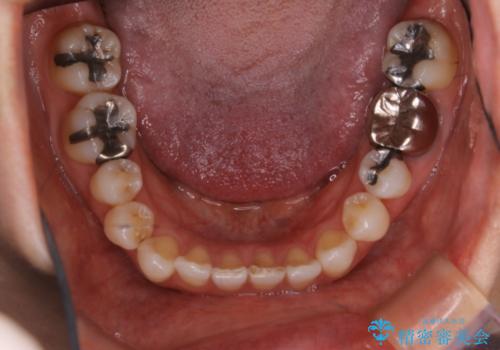

- 右上の小臼歯が二本とも90度捻じれてしまっており、奥歯の噛み合わせに問題が生じていました。

今回は右上の奥歯に入っていた銀歯の形が悪く、そのせいで歯を並べるスペースが足りない状態でした。

右上の歯の被せ物を作りなおし、適切な歯の大きさに代えてあげることによってスペースを作りました。

また、それだけではスペースが足りない為右上の奥歯は遠心移動を行っています。